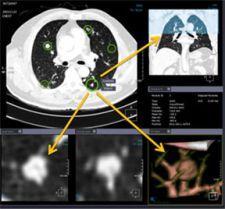

Xelis-Lung Solution improves utilization of MDCT (multi-row detector Computed Tomography) data and offers automated nodule detection for both solid and GGO (Ground Glass Opacity) -type nodules. It provides automatic 3D nodule volume measurements and other key statistics useful in nodule classification. The system provides three viewing modes: one for manual-detected nodule review followed by manual-detected nodule review followed by auto-detected review, and one for concurrent manual and automatic detection review.

Additional features that are designed to enhance radiologist workflow and ensure accurate diagnosis include the ability to select from various viewing layouts, an easy-to-use segmentation tool, the ability to insert annotations or label each nodule, and automatic job-save to store the working context.